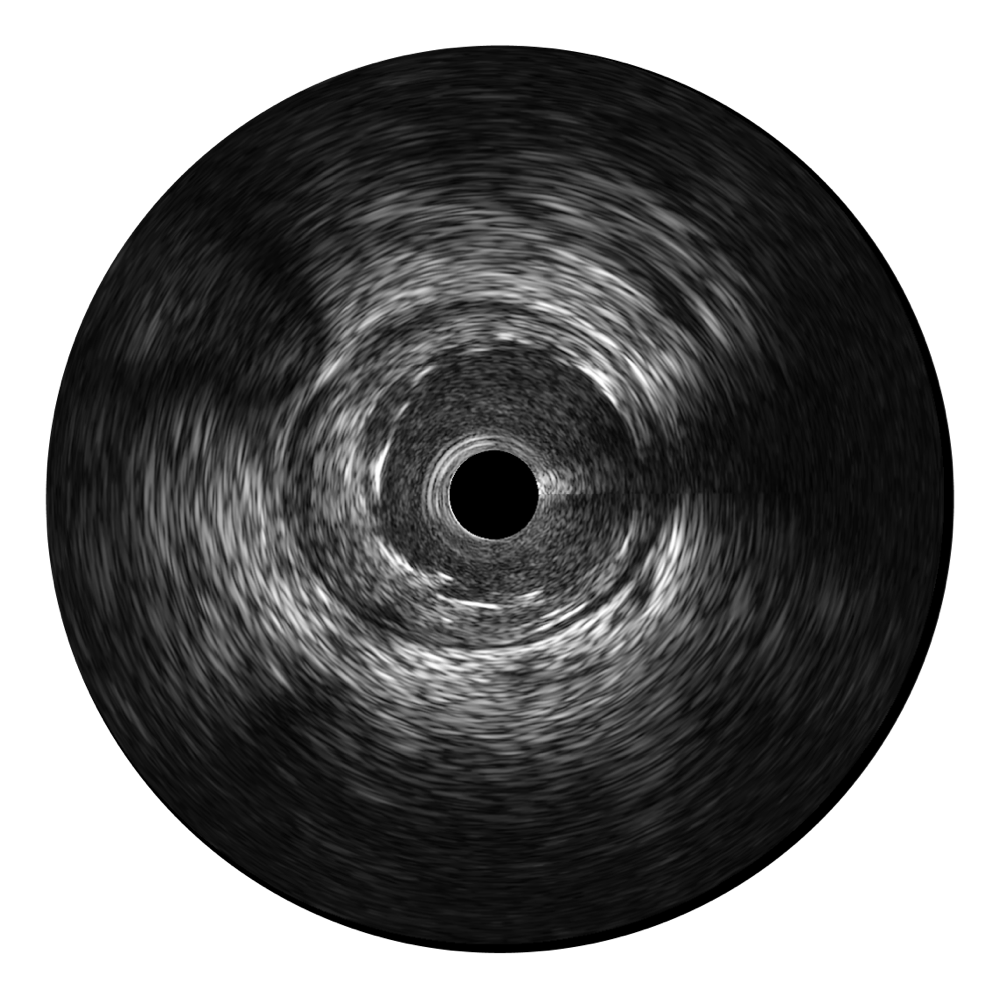

传统IVUS图像

对比传统IVUS导管成像,db真人体育官网宽频IVUS图像的近场支架梁显影更细腻,远场中膜外血管仍清晰可辨,兼顾远中近,兼顾分辨力与穿透深度